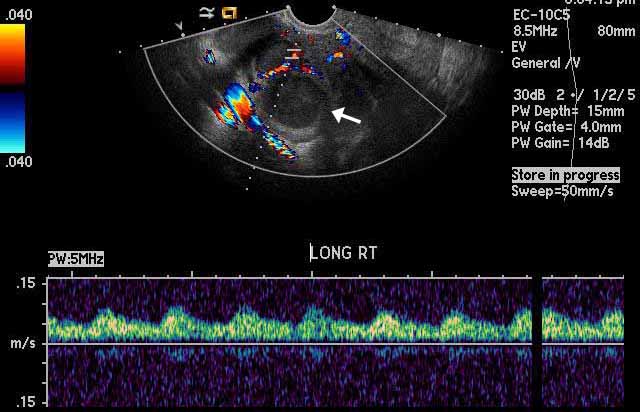

Image 3

Right tubo-ovarian abscess. The black arrow points towards a hypoechoic structure representing a combined complex collection encompassing both fallopian tube and ovary. Note that the abscess, marked by the green calipers, is characterized by a thick wall and central echogenic fluid representing pus. |

|

Image 4

Right tubo-ovarian abscess. Color Doppler shows that there is no flow within the hypoechoic right adnexal structure ( white arrow ) that represents the abscess. This indicates that the structure is a fluid filled mass as opposed to a solid mass. |